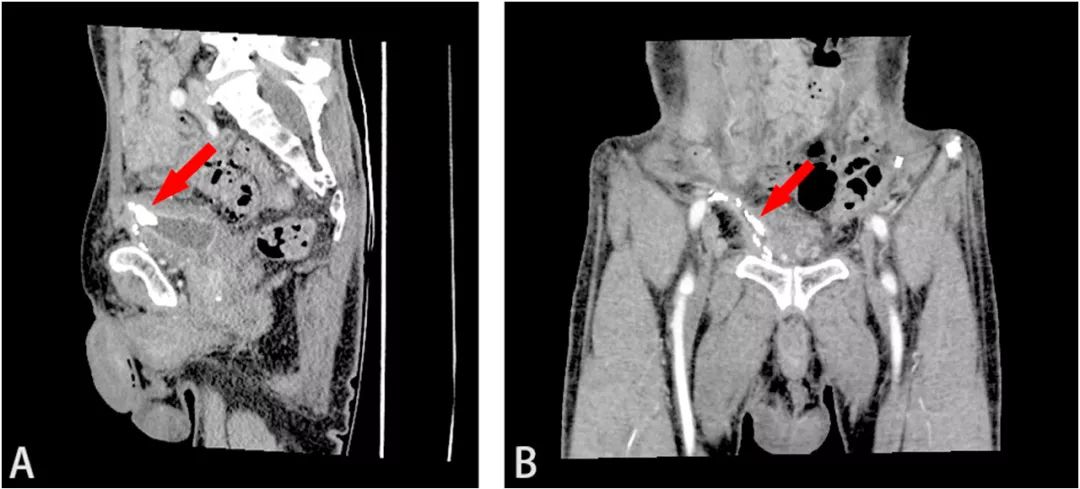

最初医生认为是膀胱憩室结石。进一步行增强CT检查显示,膀胱前壁上附着一大小约17×14×10mm的结石,骨盆内有多个金属钉,怀疑是用于固定补片的手术钉(图1B)。三维重建CT(3D-CT重建)显示补片侵蚀膀胱,结石与网片粘连紧密(图2)。膀胱镜检查证实膀胱结石的存在,结石周围有红斑性病变,但未发现补片。病变活检显示炎症反应,无恶性肿瘤。结合症状、病史和检查结果,医生最终做出“腹股沟疝修补术后补片移位致膀胱结石形成”的诊断。

图2 (A)CT矢状位和(B)冠状位。3D-CT重建显示补片侵蚀膀胱,结石与网片紧密粘连(红色箭头)